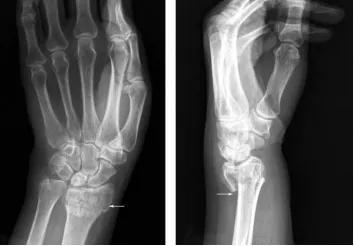

X线能清楚地拍出骨性结构(下图中白色轮廓清晰部分)但却不能清晰地分辨出软组织结构(边缘白色模糊部分)。因此,在常规摄片排除骨折表现后,患者通常会把受伤局部的肿胀、疼痛及运动障碍等不适,统称为“伤筋”,医学上则称为“软组织损伤”。

图1 手部X线片(白色部位为骨骼,边缘白色模糊部分为软组织)图片来源:X线读片指南——王书轩、范国光主编